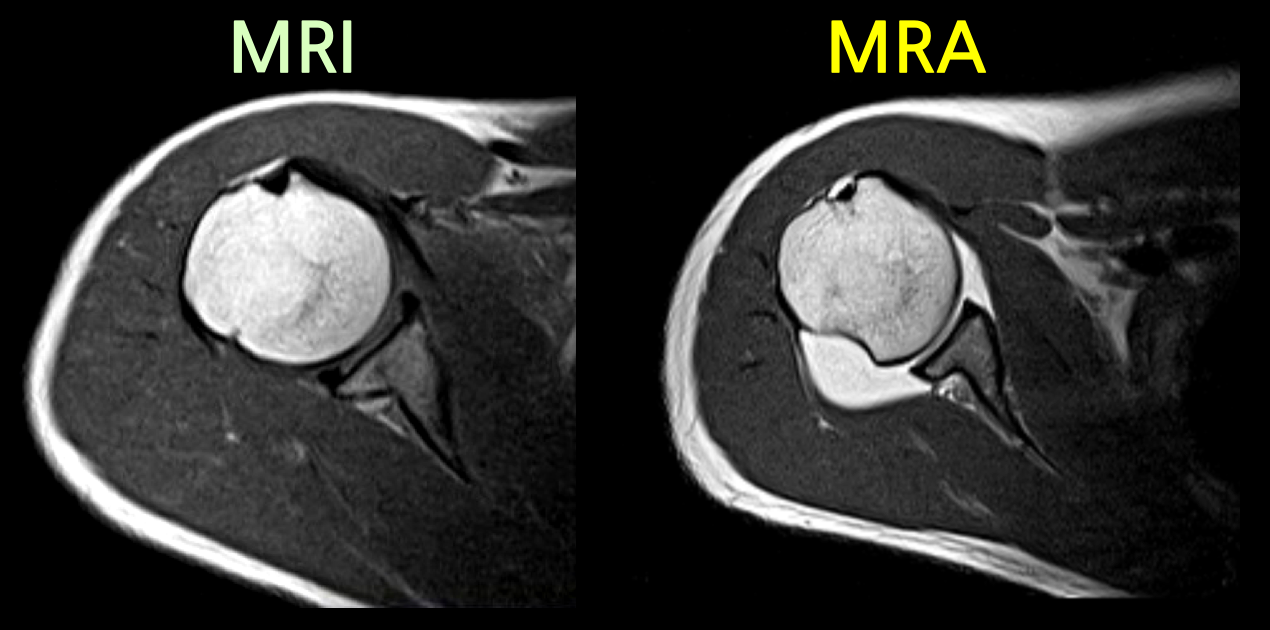

MRA는 MRI와는 다르게 조영제를 사용하며 특히, 같은 부위를 촬영하더라도 조영제 유무에 따라서 촬영된 영상 이미지에 큰 차이가 존재합니다.

정형외과에서 MRA는 어깨, 팔꿈치, 발목과 같은 관절에 적용합니다. 초음파로 확인하기 어려운 관절 전체구조를 확인하고 관절 내 이상소견 및 연부조직 손상여부, 감염등을 확인하는데 큰 도움을 줍니다.

어깨, 팔꿈치, 발목 관절에 조영제를 주입하여 MRI를 촬영하면 조영제가 손상된 틈으로 스며들어 관절 속 미세한 병변까지 진단할 수 있습니다. 이를 관절조영증강 MRI 또는 MRA(Magnetic Resonance Arthrogram)이라고 부릅니다.

- 어깨 : 회전근개 파열, 관절와순 및 관절연골 손상, 관절낭(관절막)의 유착